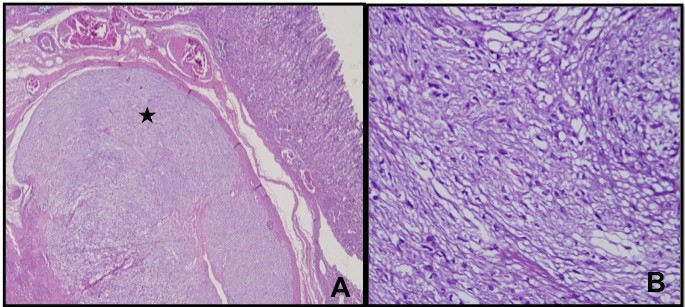

Microscopy showed nests and sheets of spindle cells infiltrating the muscularis propria. The cells have elongated nuclei, with fine chromatin, inconspicuous nuclei and moderate amount of pale eosinophilic and fibrillary cytoplasm (Figure 2). Mitotic count was 0 to 1 per 50 high power fields. However, areas of necrosis were seen in the specimen (Figure 3). The immunohistochemical stains done showed diffusely positive CD117 and DOG1, and negative for Desmin and S100, supporting the diagnosis of gastrointestinal stromal tumor (Figure 4). Based on the National Comprehensive Cancer Network (NCCN), it was stratified as having very low risk for progressive disease.

Figure 2. Figure 2. Microscopic sections of gastric mass. (A) Gastric mass at 10x magnification; (B) Gastric mass at 40x magnification.